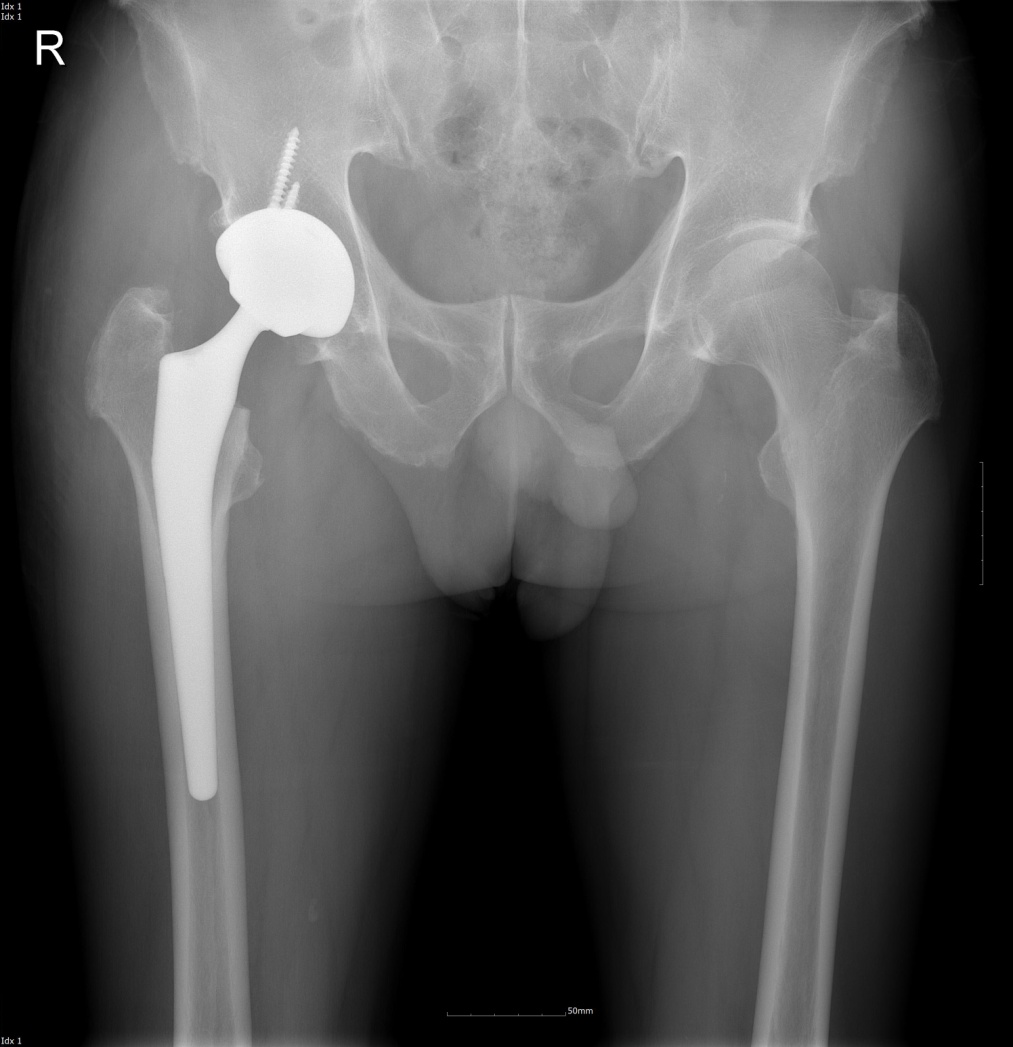

고관절 인공 관절 치환술 이해하기

고관절 인공 관절 치환술은 고관절의 퇴행성 변화나 심각한 부상으로 인한 통증과 기능 장애를 해결하기 위한 수술적 방법입니다.

고관절 인공 관절 치환술은 손상되거나 퇴행성 변화를 겪은 고관절을 인공 관절로 교체하는 수술입니다. 이 수술은 고관절의 통증을 줄이고, 움직임을 개선하는 데 목적이 있습니다.

인공 관절 삽입: 대퇴골과 골반의 비구 부위에 맞는 인공 관절을 삽입합니다. 이는 금속, 세라믹, 플라스틱 등 다양한 재료로 만들어집니다.